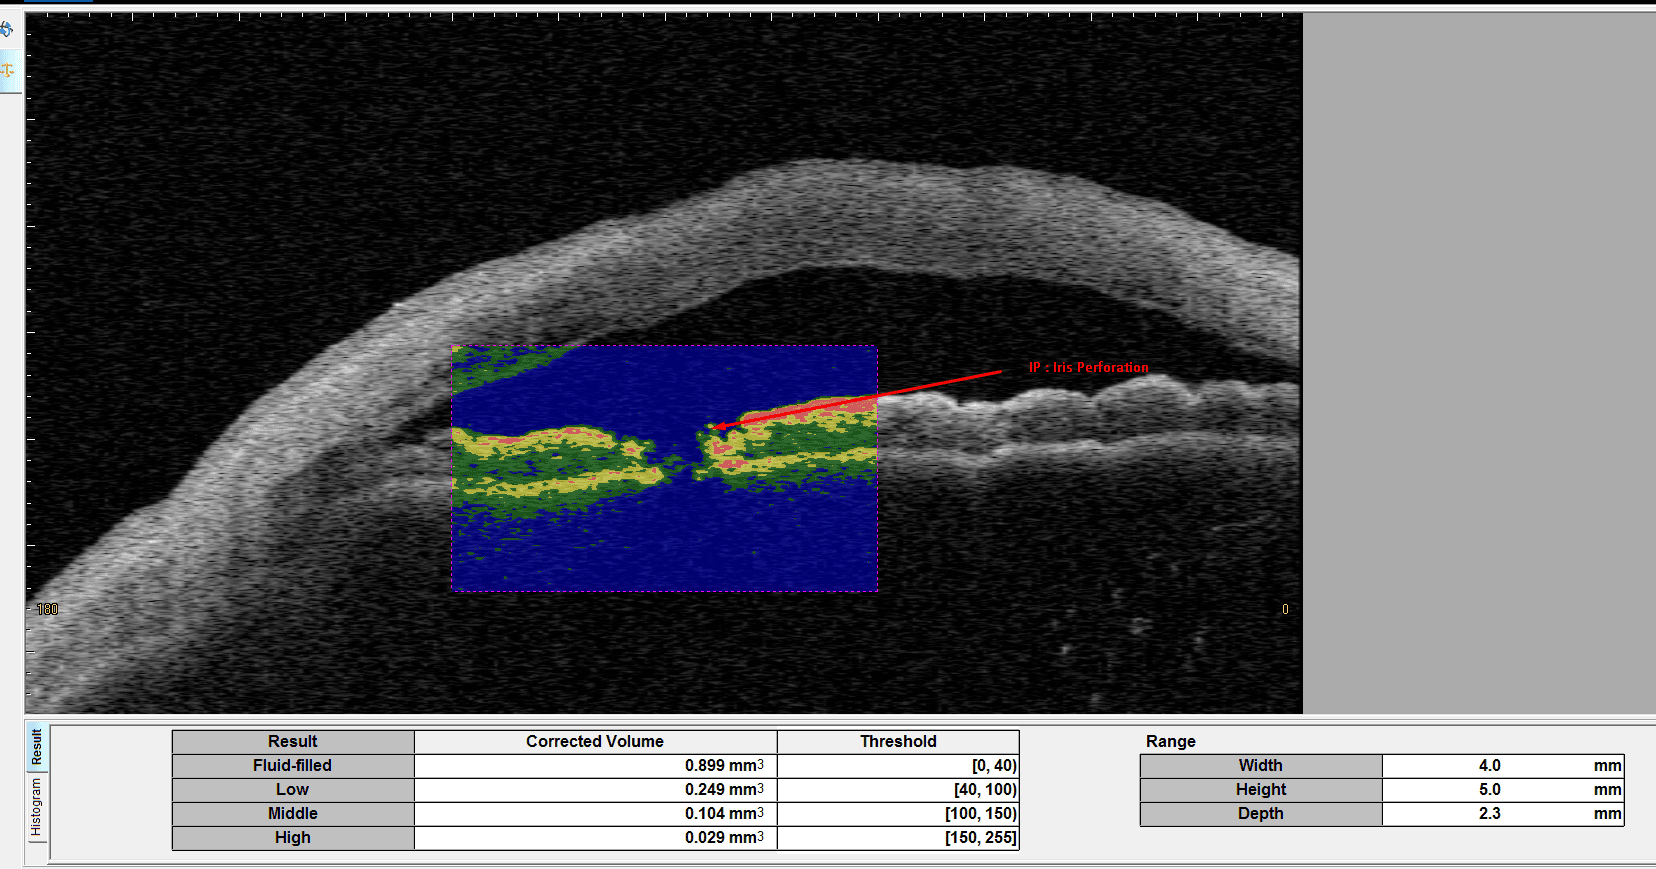

Iridotrabecular contact (ITC)

STAR Analysis - Glaucoma Application: Automatically measures the anterior chamber angles all around the anterior segment with automatic scleral spur detection, providing specific parameters needed to detect and treat glaucoma

Comprehensive corneal analysis with layer detection